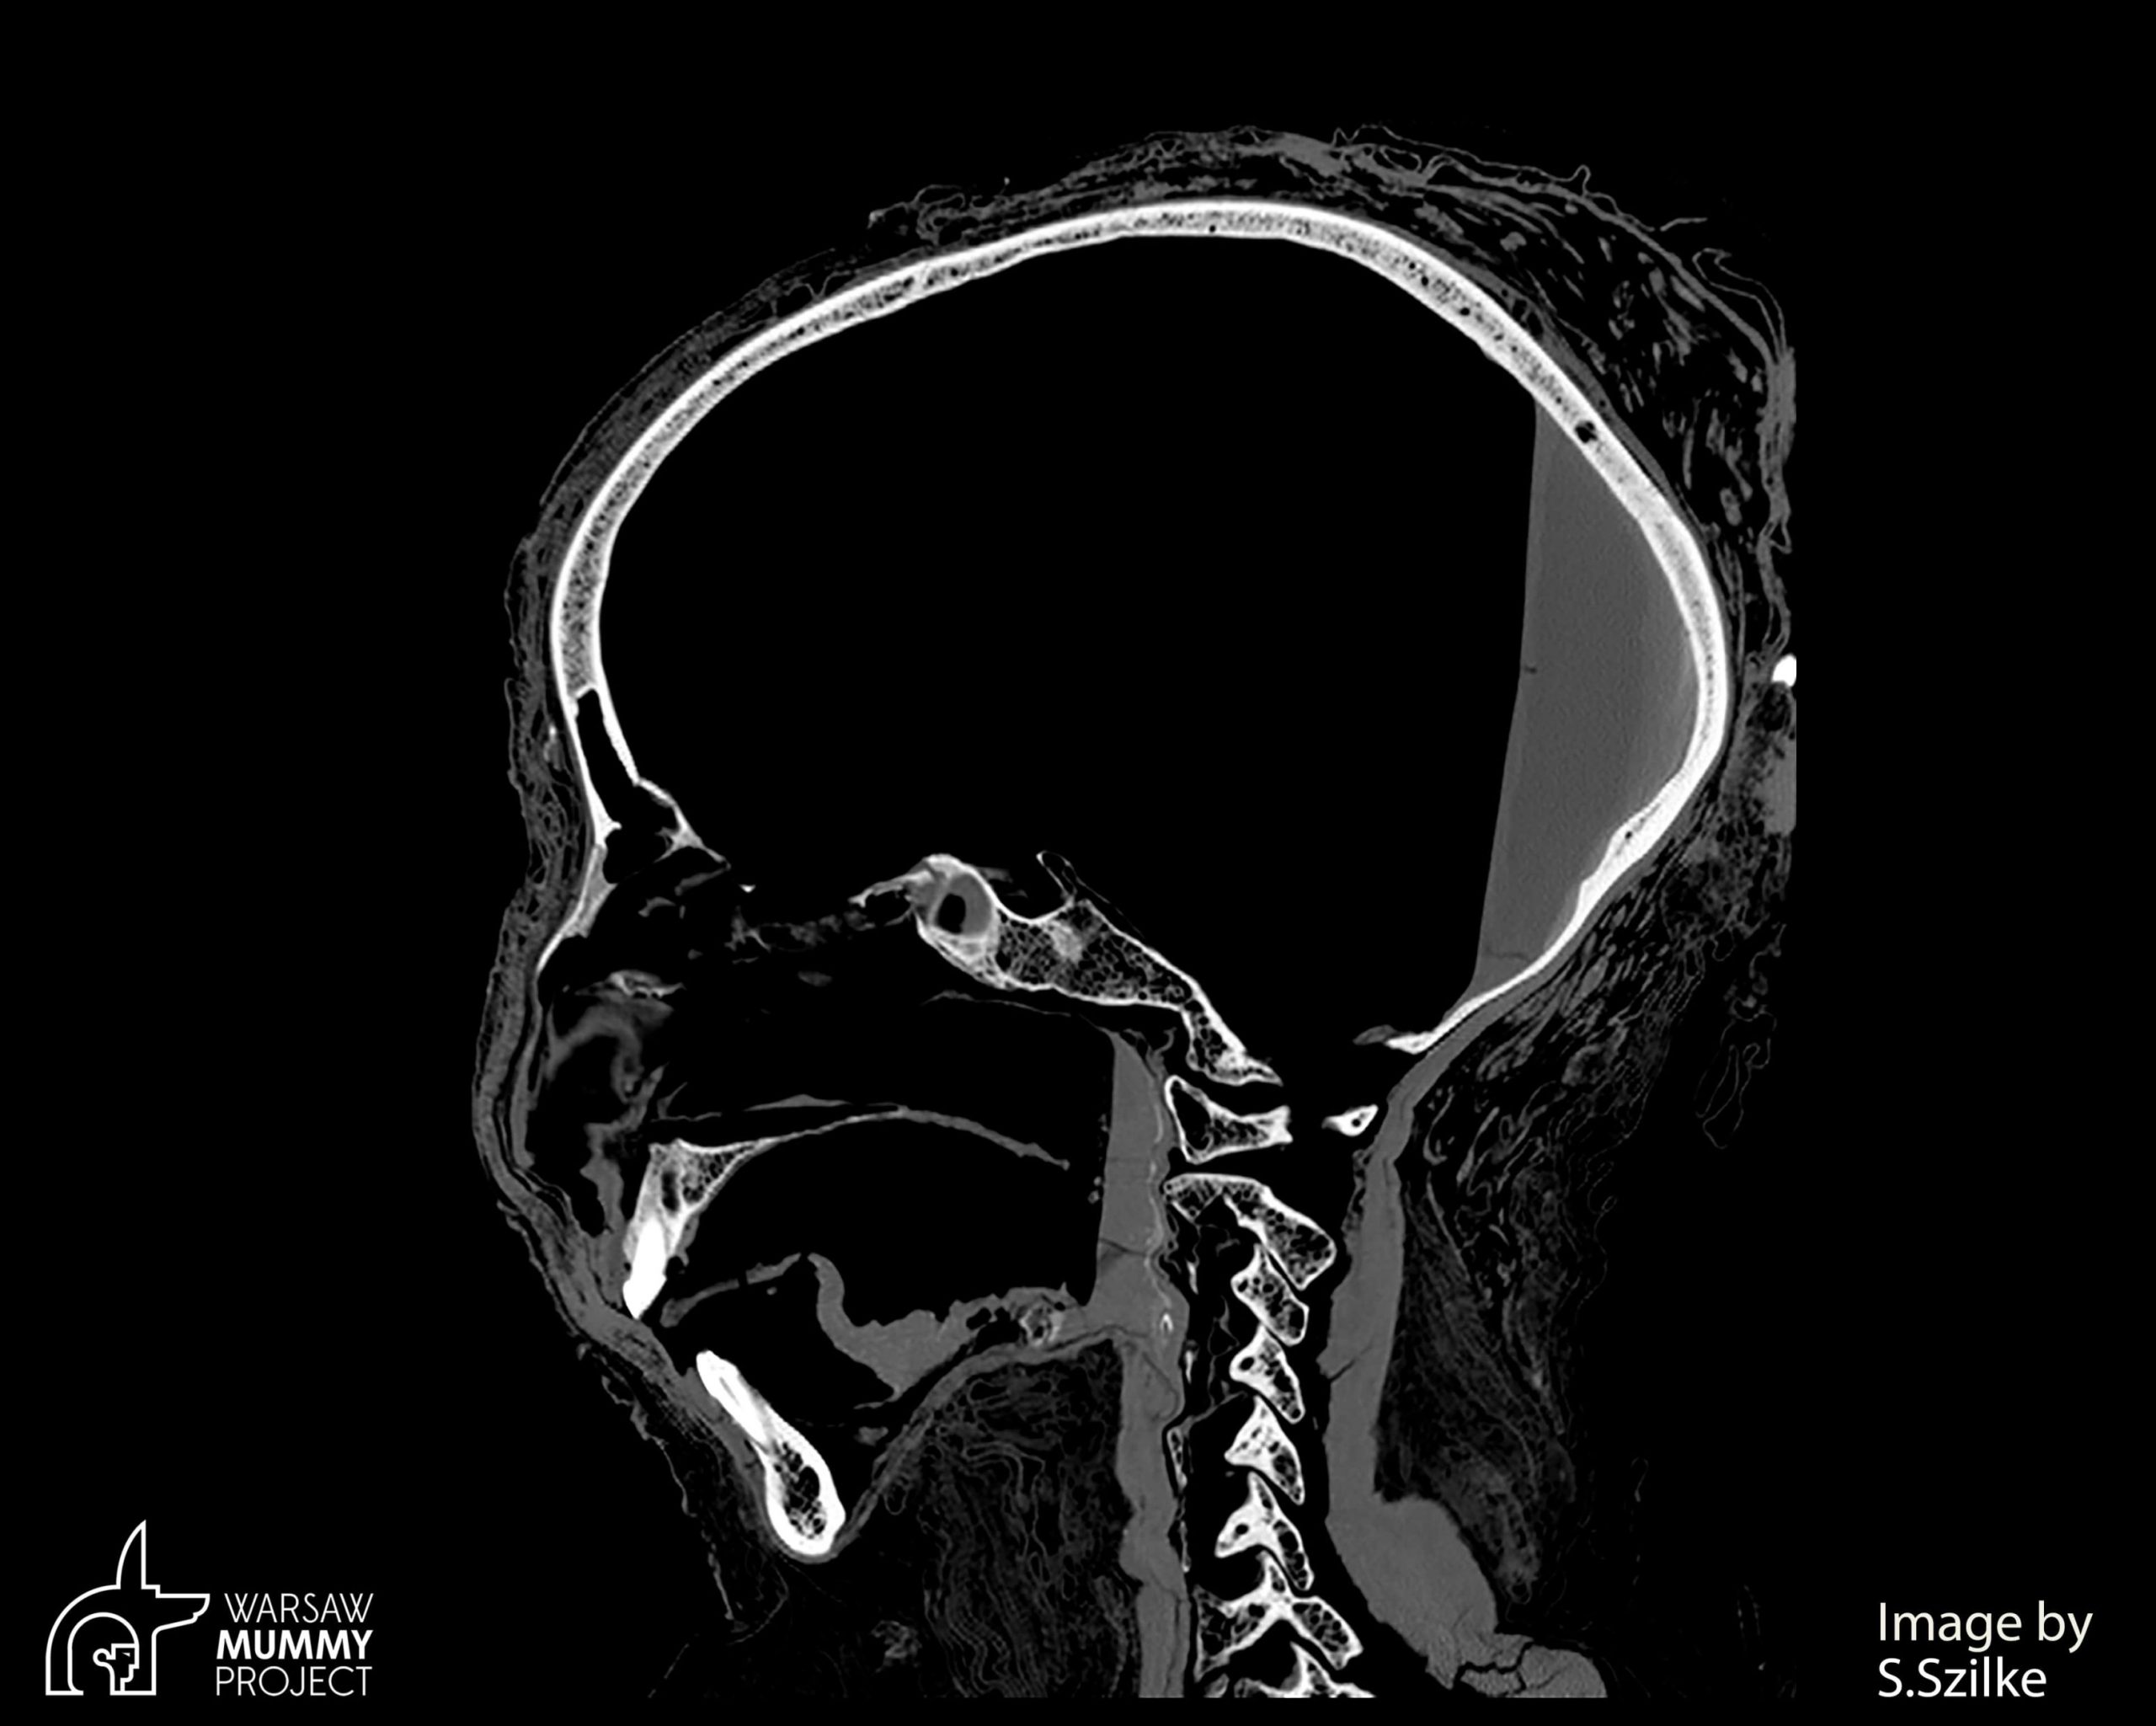

Cercetătorii de la Universitatea Shandong și de la Universitatea din Wisconsin-Madison au conceput un hidrogel injectabil care conține nanoparticule care vizează celulele stem ale gliomului.

Acestea sunt considerate principalul vinovat pentru recidiva glioblastomului, o tumoare extrem de invazivă din creier, ce apare după îndepărtarea pe cale chirurgicală a tumorii iniţiale.